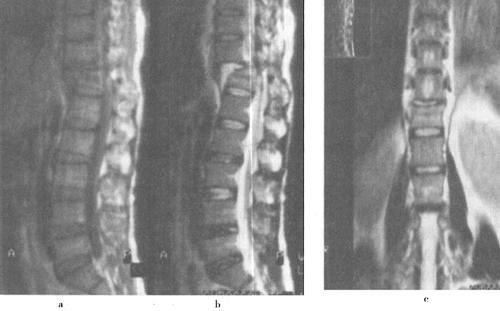

急性脊髓创伤常由于脊柱结构破坏(图7-12a和b),如撕裂伤、横断伤或严重挫伤,也可由内在的可逆性损伤如震荡或轻微挫伤引起,还可以由外来的可逆损伤如脊髓受压引起(图7-13)。按损伤程度分为脊髓震荡伤、脊髓挫伤、脊髓撕裂伤和横断伤。

图7-12a 颈段脊髓横断性损伤。颈椎正侧位片:C5以上前脱位,该水平段椎管狭窄,可推测脊髓受压迫

图7-12b MRI矢状面T1WI可见颈髓在C5水平明显受压,椎体前缘和椎管内可见中等偏高信号,局部颈髓可见斑点状高信号;12WI被压迫的脊髓亦见高信号出血灶,脊椎前方前纵韧带下血肿,呈高信号

图7-13 胸椎压缩性骨折伴脊髓压迫:T1WI和T2WI示T10压缩性骨折后凸畸形,脊髓压迫